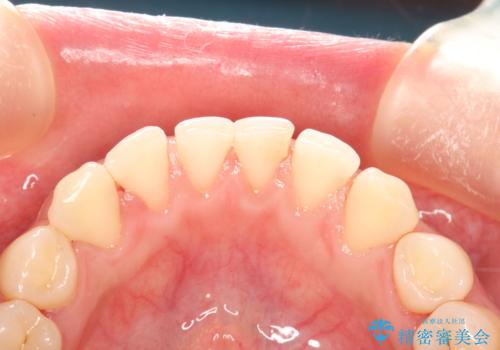

終了時

かなり久しぶりの歯科医院との事で、全体的に古くからの歯垢・歯石が多く付着していたため、自費クリーニング(PMTC)60分コース・歯周ポケット検査(保険適応)を行いました。

磨き残しが放置されると、そこで病原菌が繁殖し始めます。よって歯肉に炎症が生じ、歯周病の原因になることがあります。

定期的に、歯周病検査や専門的なクリーニングをすることで、早期発見につながります。